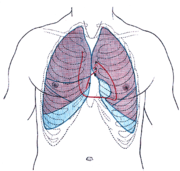

Puls (tep) je tlaková vlna, která je vyvolaná vypuzením krve z levé srdeční komory do srdečnice (aorty), odkud se šíří dalšími tepnami do celého těla. V lékařství série těchto vln odpovídá srdečnímu rytmu a frekvenci.

Puls lze nahmatat na větších tepnách blízkých povrchu těla, nejčastější tepnou pro měření pulsu je krkavice (arteria carotis), vřetenní tepna (arteria radialis), zápěstní tepna (arteria ulnaris), při nedostatečném dokrvovaní horních končetin se používá pažní tepna (arteria brachialis) a na dolních končetinách stehení tepna (arteria femoralis).